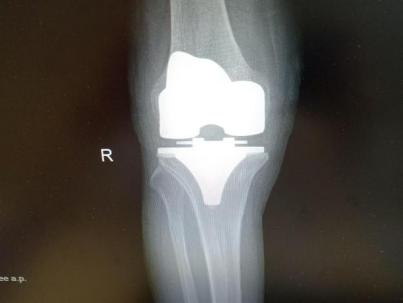

为提升区域内基层医疗机构糖尿病足诊疗服务能力、促进青年医师对糖尿病足的规范化诊治水平,遵义市第二城市医疗集团总院(贵州航天医院)圆满举办贵州省继续医学教育项目——胫骨横向骨搬移技术治疗糖尿病足专题研讨班。 贵州航天医院党委委员、副院长彭亮出席会议并致辞,遵义市第二城市医疗集团各成员单位,以及红花岗区、汇川区、绥阳县、桐梓县等多个区县的基层医疗机构骨干医师参加会议。 研讨班 本次研讨班以胫骨横向骨搬移技术在糖尿病足治疗中的应用为核心主题,围绕糖尿病药物治疗与生活方式管理策略、围手术期血糖精准调控要点、胫骨横向骨搬移技术典型病例深度解析、糖尿病足的临床分型与个体化治疗方案制定等临床实践中的热点与难点展开深入探讨,通过专题授课、案例研讨、互动交流等多元化形式,为参会者搭建了理论与实践结合的学习平台。 此次研讨班不仅为区域内基层医院搭建了学术交流与经验共享的平台,更对推动糖尿病足预防、诊断与治疗的规范化、系统化发展起到了积极作用,有效助力青年医师更新专业知识体系、提升临床技能,为进一步保障区域内糖尿病足患者的健康奠定了坚实基础。 贵州航天医院骨科专家简介 陈明勇 骨一科主任,副主任医师 临床擅长:从事创伤骨科工作约20年,对骨缺损、骨不连、骨肿瘤、肢体畸形等的肢体矫形重建及功能重建,慢性化脓性骨髓炎的根治治疗、糖尿病足的保肢治疗、快速康复理念(ERAS)下的老年骨折的诊治,四肢复杂骨折的诊治,四肢骨折等微创手术治疗具有丰富的临床经验。 2004年毕业于遵义医学院临床专业,曾在中国人民解放军总医院、广西医科大学第一附属医院、上海第六人民医院骨科进修。中国中西医结合学会骨伤科专业委员会横向骨搬移治疗糖尿病足及微血管网再生学组首届委员,遵义市医学会创伤分会常务委员。 瞿 晖 骨科党支部书记,骨二科主任,副主任医师 临床擅长:对骨科的常见病、关节外科、脊柱外科及运动医学疾病的诊治具有丰富的临床经验,熟练掌握骨科手术操作技术。 毕业于遵义医学院临床医学系,2005年前往广州中山大学第一附院骨显微医学部进修学习,2011年前往成都华西医院进修学习,并多次在省内外学习骨科相关知识,是中华医学会骨科分会会员。 赵小锋 中共党员,骨二科副主任,副主任医师 临床擅长:从事骨科临床工作11年,对骨科常见病、多发病诊疗有较为丰富的临床经验,擅长脊柱相关疾病诊断及治疗,尤其是颈、腰、腿疼痛疾病诊断及治疗,擅长胸腰椎骨折微创经皮穿刺内固定术、经皮穿刺椎体成形术、经皮穿刺脊柱内镜下腰椎间盘摘除术、单纯开创腰椎间盘摘除术、腰椎滑脱复位椎间植骨椎融合内固定术、腰椎管狭窄减压融合内固定术及人工髋、膝关节置换术等。 2012年毕业于遵义医学院外科学专业硕士研究生,2019年参加“遵义市115医学人才精英计划”于上海交通大学第一附属医院培训学习,2023年于北京大学第三人民医院脊柱外科进修学习,曾获得遵义市优秀医师荣誉称号。 遵义市手外科第一届委员,遵义市医学会创伤分会第一届委员,遵义市医学会创伤分会第二届委员,贵州省康复医学会第三届脊柱脊髓专业会委员,遵义市医学会烧伤与整形外科学分会委员,发表论文5篇,其中国家级核心期刊1篇,SCI论文1篇,主持市级课题1项并结题,参与市级课题2项。 赵兴东 骨科主任医师 临床擅长:擅长骨科的常见病及各种创伤、四肢骨折创伤修复、骨感染、手足疾病的诊治和手足体表畸形的矫形整复,熟练掌握骨科四肢骨病及创伤的手术操作技术,尤其在四肢关节复杂性损伤、手足外伤、组织缺损创面、难治创面的皮瓣修复方面及平足、高弓足矫形方面及四肢慢性疼痛诊治、康复方面具有丰富的临床经验。 硕士研究生,毕业于遵义医学院临床外科系,2015年前往山东省立医院手足外科进修学习;遵义市医学分会创伤分会第一、二届委员,遵义市手外科医学会第二委届员会常务委员;在省级及省级以上期刊发表文章9篇,参编著作2部,参与主持并完成市级课题1项,参与市级课题2项、省级课题1项。 张艳金 中共党员,骨科副主任医师 临床擅长:从事骨外科工作16年,对复合伤、多发伤的救治、四肢骨干骨折、关节周围骨折、骨肿瘤、骨髓炎等诊治具有丰富的临床经验。 中共党员,硕士研究生,2006年本科毕业于山西医科大学第二临床医学院,2011年研究生毕业于北京军区总医院;在“老年COPD患者合并髋部骨折的诊治”国际合作课题组研究两年,在老年髋部骨折的诊治方面具有丰富的经验,并发表论文6篇;主持遵义市级课题1项,承担遵义医科大学的临床教学工作,获得遵义医科大学优秀带教老师荣誉。编撰有《骨科疾病诊疗精粹》一书,开展2项新技术,编撰地方规范《务川自治县创伤骨科常见疾病诊疗规范》一书。 张俊凯 骨科副主任医师 临床擅长:从事骨科临床工作28年,对创伤骨折、骨感染、骨缺损、骨不连等外科诊治,四肢骨折的微创手术治疗,四肢复杂骨折(如关节内粉碎性骨折、多发骨折等)的损伤控制及手术治疗等具有丰富的临床经验。 1995年毕业于遵义医学院临床专业,2009年前往复旦大学附属医院骨科进修1年。 卢懿明 中共党员,骨科副主任医师 临床擅长:从事骨科工作18年,对创伤骨折、四肢骨折的微创手术治疗、四肢复杂骨折(如关节内粉碎性骨折、多发骨折等)的损伤控制及手术治疗,尤其是髋部骨折的PFNA等微创技术,踝关节骨折、膝关节周围骨折的Mipo微创技术等具有丰富的临床经验,开展了4项新技术,发明6项新型专利技术。 2005年毕业于遵义医学院临床专业,2017年,前往南方医科大学第三附属医院骨科进修半年,回院后运用Mipo技术对骨干骨折及干骺端骨折的治疗技术,同时积极开展骨盆骨折、髋臼骨折腹直肌外侧切口的应用;发表了多篇专业论文,经常参与省内外学术交流会授课,获得医院荣誉称号多个。 邬夏荣 骨科副主任医师 临床擅长:从事骨科工作16年,对四肢复杂骨折、骨肿瘤的诊治,尤其是足踝创伤、慢性踝关节损伤、平足症等诊疗具有丰富的临床经验。 2006年毕业于遵义医科大学临床医学专业,曾在陆军军医大学西南医院进修学习,发表多篇骨科学术论文。 余德怀 中共党员,骨科副主任医师 临床擅长:从事骨科工作10余年,对运动医学、骨关节、脊柱外科常见病、多发病的诊治具有丰富的临床经验。 硕士研究生,2011年毕业于遵义医学院临床医学专业,曾前往遵义医科大学附属医院运动医学专业进修学习;是贵州省医学会运动医学分会青年委员,西部关节镜联盟委员;发表多篇骨科学术论文。 冯 乾 骨科副主任医师 临床擅长:从事骨科工作近20年,熟练掌握骨科多发病及常见病的诊治,尤其对脊柱退变性疾病的诊断及治疗具有丰富的临床经验,主要研究脊柱微创相关治疗方式,能熟练开展椎间孔镜及UBE。 曾前往北京大学第三医院进修学习疼痛及椎间孔镜、首都医科大学友谊医院专业进修脊柱内镜;是贵州省康复医学会第三届脊柱脊髓专业委员会委员;发明专利3项、发表脊柱外科专业论文多篇。 贵州航天医院骨科简介 基本情况 贵州航天医院(原3417医院)骨科组建于1968年,前身是以创伤和断肢(断指)再植闻名于世的上海市第六人民医院骨科,中国断肢(断指)再植的奠基者、中科院院士陈仲伟等专家莅临科室指导医疗和教学,并在70年代开展了贵州省首例断肢(断指)再植手术。组建50余年来,诊治患者已逾百万,挽救了无数的伤病员,成为了保障遵义地区人民群众健康的重要支撑。 经过几代人的不懈努力,今天的骨科,已由创伤骨科发展至骨病、骨肿瘤、骨结核等领域,现有脊柱外科、关节外科、四肢创伤、手足外科四个亚专科,成为了集医疗、教学、科研于一体的综合学科,是贵州省临床重点专科、遵义市临床重点专科、遵义市骨科临床医学中心、遵义市基层骨科专科联盟理事长单位。 科室目前开放床位110张,共有医护人员50余人,副高级以上专家18人,硕士研究生15人。拥有一流骨科医疗设备多台,每年不定期选派优秀技术骨干到全国各大知名医学院校进修、学习、参观、交流,并邀请国内、国外知名专家教授来院进行交流、指导,通过不断引进国内外先进的诊疗技术,科室医疗技术水平稳步提升,为广大人民群众提供了优质的医疗服务。 专科特色 骨一科 (一)骨缺损、骨不连的肢体与功能重建 胫骨横向骨搬移技术治疗糖尿病足: (二)慢性骨髓炎的根治治疗 (三)肢体缺血性疾病如糖尿病足、脉管炎的保肢治疗 (四)皮瓣修复 (五)复杂创伤的治疗 (六)老年髋部骨折及小儿骨折快速手术 老年髋部骨折: 骨二科 (一)胸腰椎骨折微创经皮椎弓根螺钉固定术 (二)老年性骨质疏松性患者腰椎滑脱脊柱内固定术(骨水泥螺钉) (三)V形双通道脊柱内镜技术(VBE)腰椎融合术治疗腰椎退行性疾病 (四)老年性骨质疏松性骨折(PVP/PKP)术 (五)人工髋关节置换术 (六)双侧股骨头坏死人工全髋关节置换 (七)右侧全髋置换术后假体周围骨折翻修 (八)人工膝关节置换术 (九)人工膝关节假体松动翻修 (十)关节镜技术 传统手术切口 关节镜技术切口 诊疗范围 骨一科 1.四肢创伤、矫形。 2.手、足踝外科。 骨二科 End